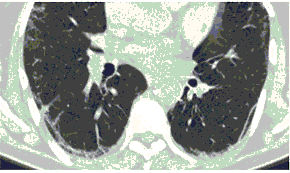

2. Наличие клинических проявлений, указанных в п. 1, в сочетании с характерными изменениями в легких по данным компьютерной томографии (КТ) (см. Приложение 1 настоящих рекомендаций) вне зависимости от результатов однократного лабораторного исследования на наличие РНК SARS-CoV-2 и эпидемиологического анамнеза.

- Изменения при КТ (рентгенографии), типичные для вирусного поражения (объем поражения минимальный или средний; КТ 1-2)

- Изменения в легких при КТ (рентгенографии), типичные для вирусного поражения (объем поражения значительный или субтотальный; КТ 3-4)

- Изменения в легких при КТ (рентгенографии), типичные для вирусного поражения критической степени (объем поражения значительный или субтотальный; КТ 4) или картина ОРДС.

КТ имеет высокую чувствительность в выявлении изменений в легких, характерных для COVID-19. Применение КТ целесообразно для первичной оценки состояния ОГК у пациентов с тяжелыми прогрессирующими формами заболевания, а также для дифференциальной диагностики выявленных изменений и оценки динамики процесса. КТ позволяет выявить характерные изменения в легких у пациентов с COVID-19 еще до появления положительных лабораторных тестов на инфекцию с помощью МАНК. В то же время, КТ выявляет изменения легких у значительного числа пациентов с бессимптомной и легкой формами заболевания, которым не требуется госпитализация. Результаты КТ в этих случаях не влияют на тактику лечения и прогноз заболевания при наличии лабораторного подтверждения COVID-19. Поэтому массовое применение КТ для скрининга асимптомных и легких форм болезни не рекомендуется.

15. Рекомендации по формированию описаний и оценке изменений в легких и ОГК при имеющейся/подозреваемой пневмонии COVID-19 представлены в Приложении 1.